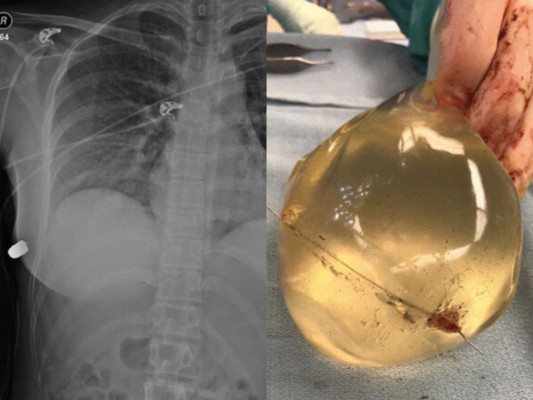

Los médicos creen que la mujer de 30 años, sobrevivió gracias a que la silicona hizo que la bala no tocara órganos vitales.

Hay dos tipos de implantes mamarios aprobados para la venta en Estados Unidos. Ambos tienen una cubierta externa de silicona, pero uno está lleno de solución salina y el otro está lleno de gel de silicona. Pueden variar en tamaño, grosor del cascarón, textura y forma de la superficie del cascarón.

“La entrada de la herida de bala estaba en el seno izquierdo, pero la fractura de costilla estaba en el lado derecho. La bala entró primero en la piel del lado izquierdo, y luego rebotó a través del esternón hacia el seno derecho y le rompió la costilla en el lado derecho”, explicó el galeno.

La mujer sufrió una herida de bala, costillas rotas e implantes rotos, pero resultó notablemente ilesa y sobrevivió.